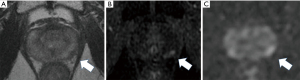

His care team excluded apparent distant metastasis per these evaluations that were available at that time, although the possibility of undetected micro dissemination could not be excluded. His care team conducted a template-guided saturation mapping (TGSM) biopsy at five-year intervals after EBRT completion. The MRI identified cancer recurrence in the right lobe of his prostate (Figure 1). Based on the MRI findings, his care team conducted a template-guided saturation mapping (TGSM) biopsy at five years interval after EBRT completion, collecting 30 samples, including the seminal vesicle. They identified poorly differentiated adenocarcinoma exclusively from the four biopsy samples of the right lobe of the prostate, which corresponded to the MRI findings (Figure 1 and Table 2). No cancer cells were located in the remaining 26 TGSM biopsy samples where prostate tissue was replaced by fibromuscular tissue indicating an EBRT effect. Based on these findings, his care team conducted salvage LDR BT with a radiation dose of 160 Gy via 125I seeds implantation to cover the MRI- and biopsy-positive lesion. The rectal volume receiving 100% of the prescribed minimal peripheral dose (R100) was 0 cc. Figure 2 presents the intraoperative dose cloud image. The dosimetric parameters of the salvage LDR BT intraoperatively and one month later are shown in Table 2 and Table 3, respectively. He experienced Grade 2 genitourinary (GU) toxicity at four months and Grade 1 gastrointestinal (GI) toxicity eight months after salvage LDR BT.

The MRI identified prostate cancer recurrence in the left posterior corner on the mid portion of the prostate (Figure 3). His care team conducted a TGSM biopsy based on the MRI findings at six-year intervals after EBRT completion, collecting 31 samples, including the seminal vesicle. They identified poorly differentiated adenocarcinoma from four biopsy samples from the left lower corner of the prostate, which corresponded to the MRI findings (Table 4). No cancer cells were located in the remaining TGSM biopsy samples where prostate tissue was replaced into fibromuscular tissue indicating EBRT effect.